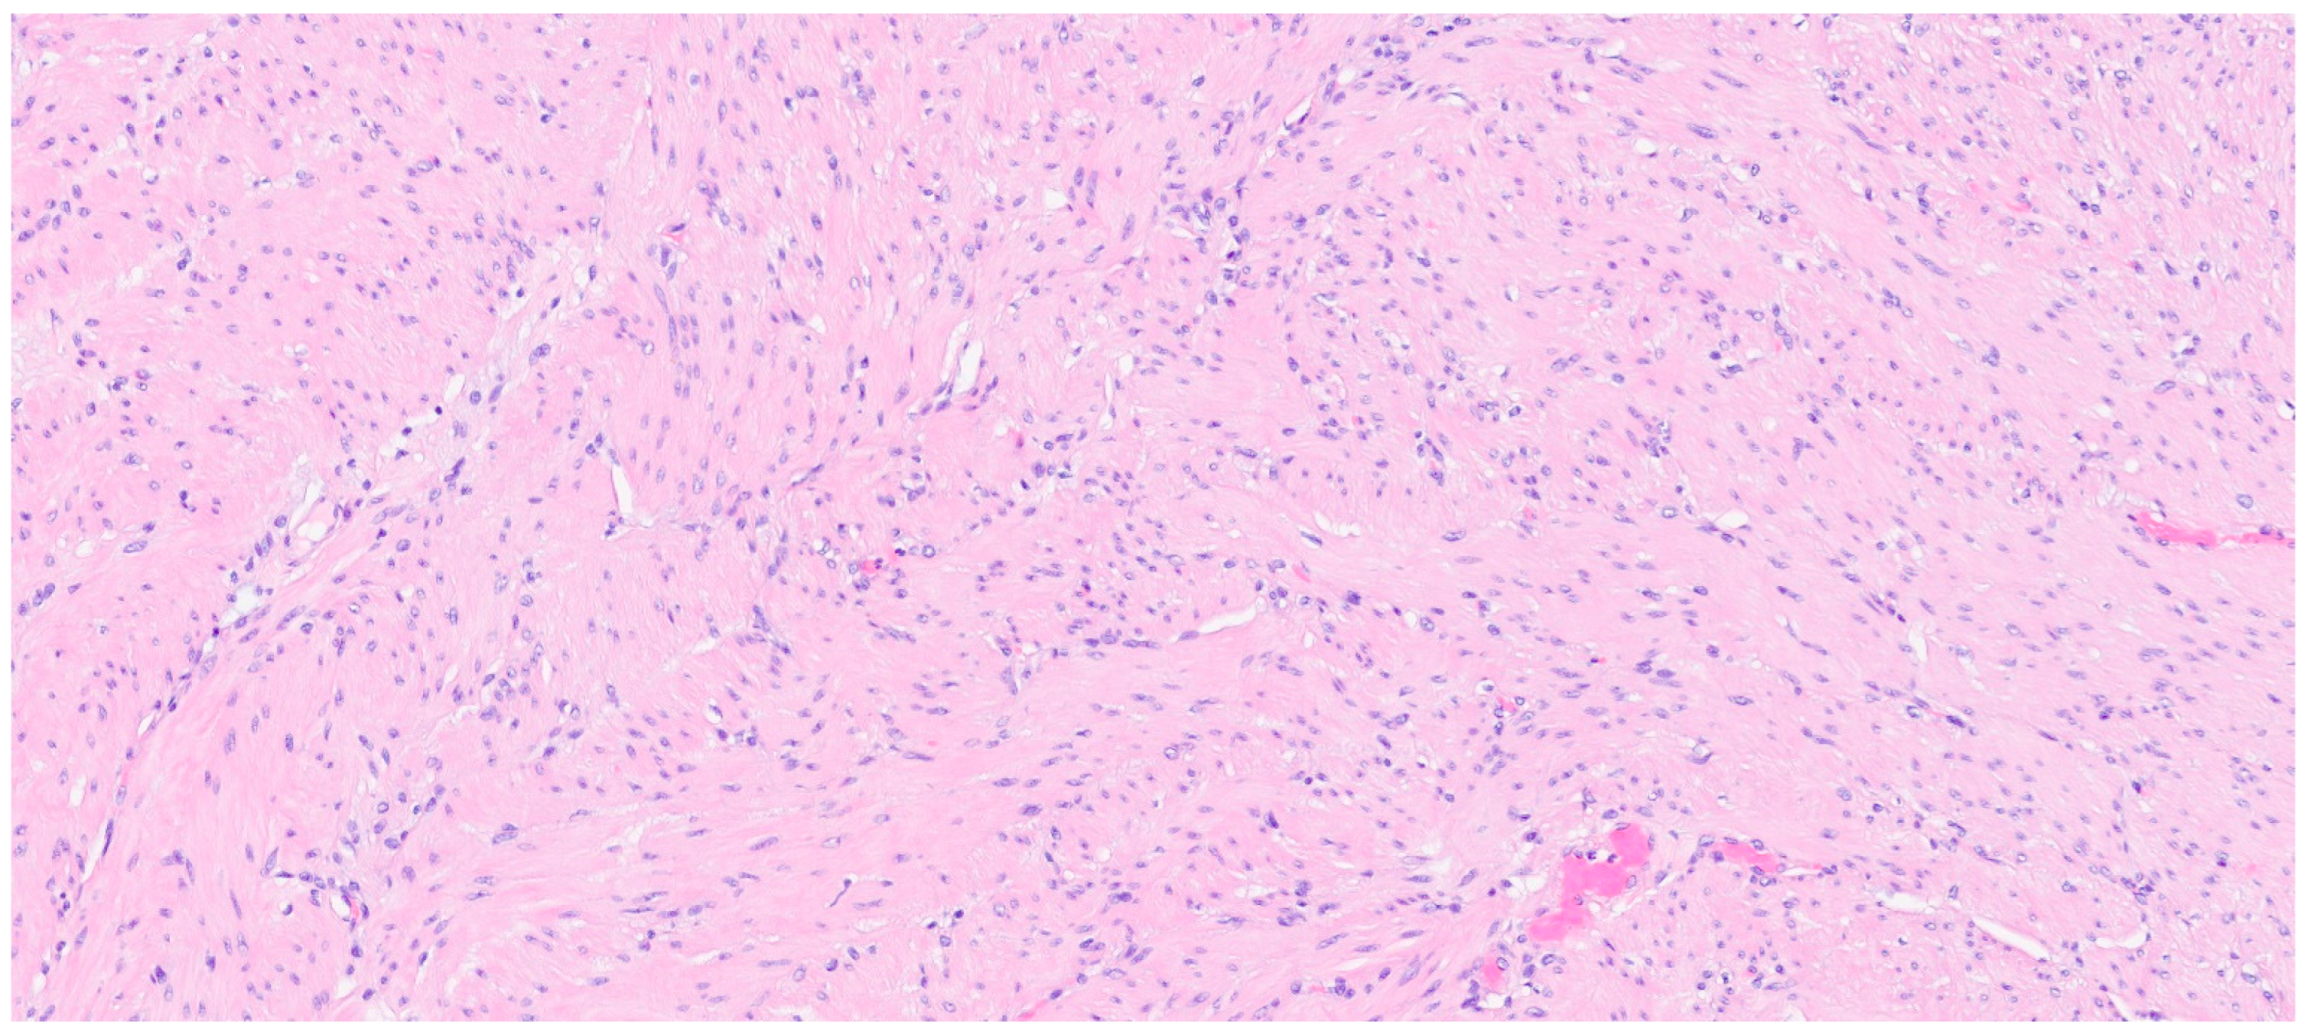

| Fibromatosis | 30 and 40 years | Mesentery of the small bowel | Abdominal pain | Long fascicles of spindle cells with ovoid nuclei without atypia or necrosis | Β-catenin |